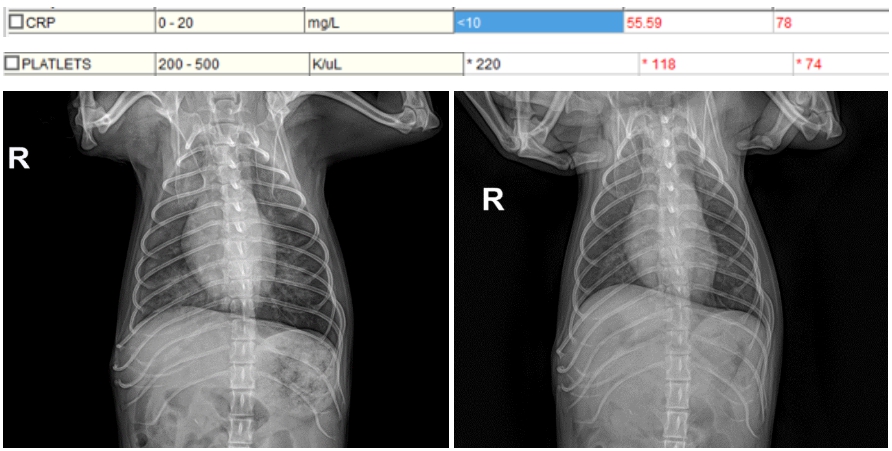

치료 4일차(좌) /치료 5일차(우)

치료 7일차에 시행한 혈액검사 수치 및 방사선 검사 결과에서 전반적인 호전 소견이 확인되었습니다.

위기였던 시기는 무사히 넘겼으며, 상태가 안정적으로 회복됨에 따라 장기적으로 IMT에 준한 내복약 복용을 병행하며 관리를 시작하였습니다.